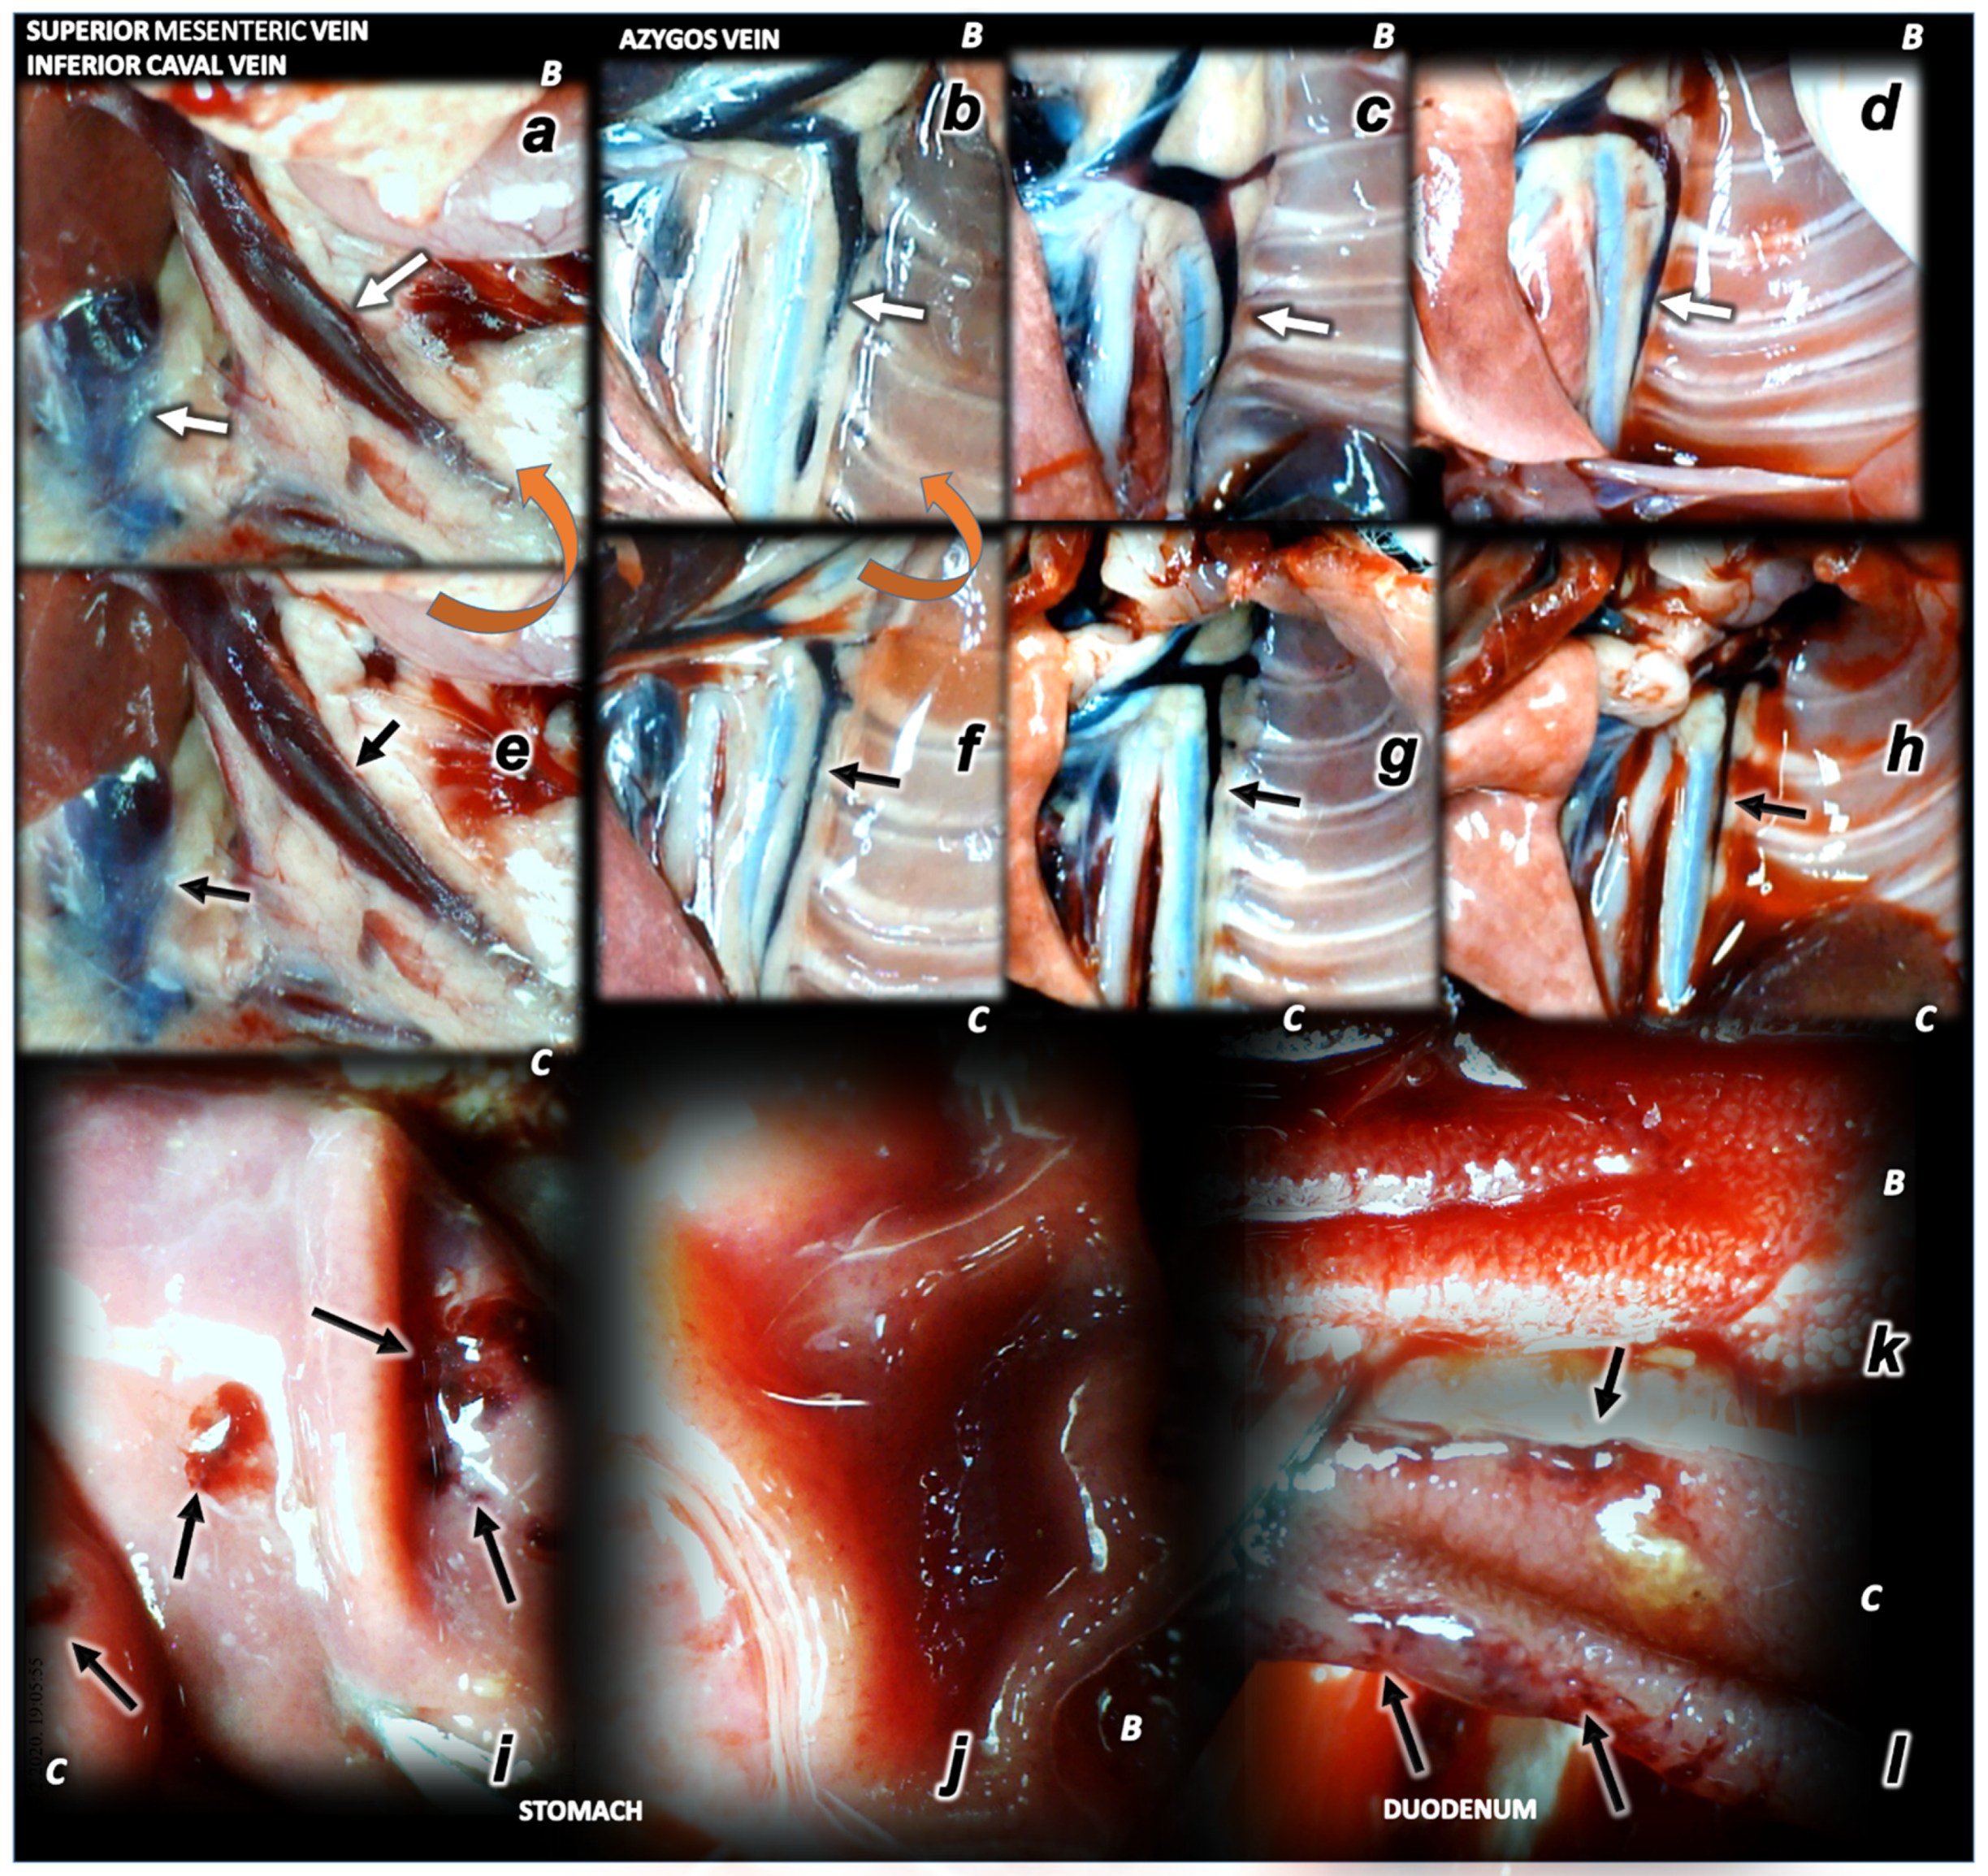

3.4. Venography in the Superior Sagittal Sinus, Right External Vein, Inferior Caval Vein

3.5. Pressure Recording Upon Additional Venous Hypertension Originated Inside the Sinus Lumen, Neck and Abdomen

3.6. Stomach, Duodenum, Liver, Spleen, Ascites Presentation